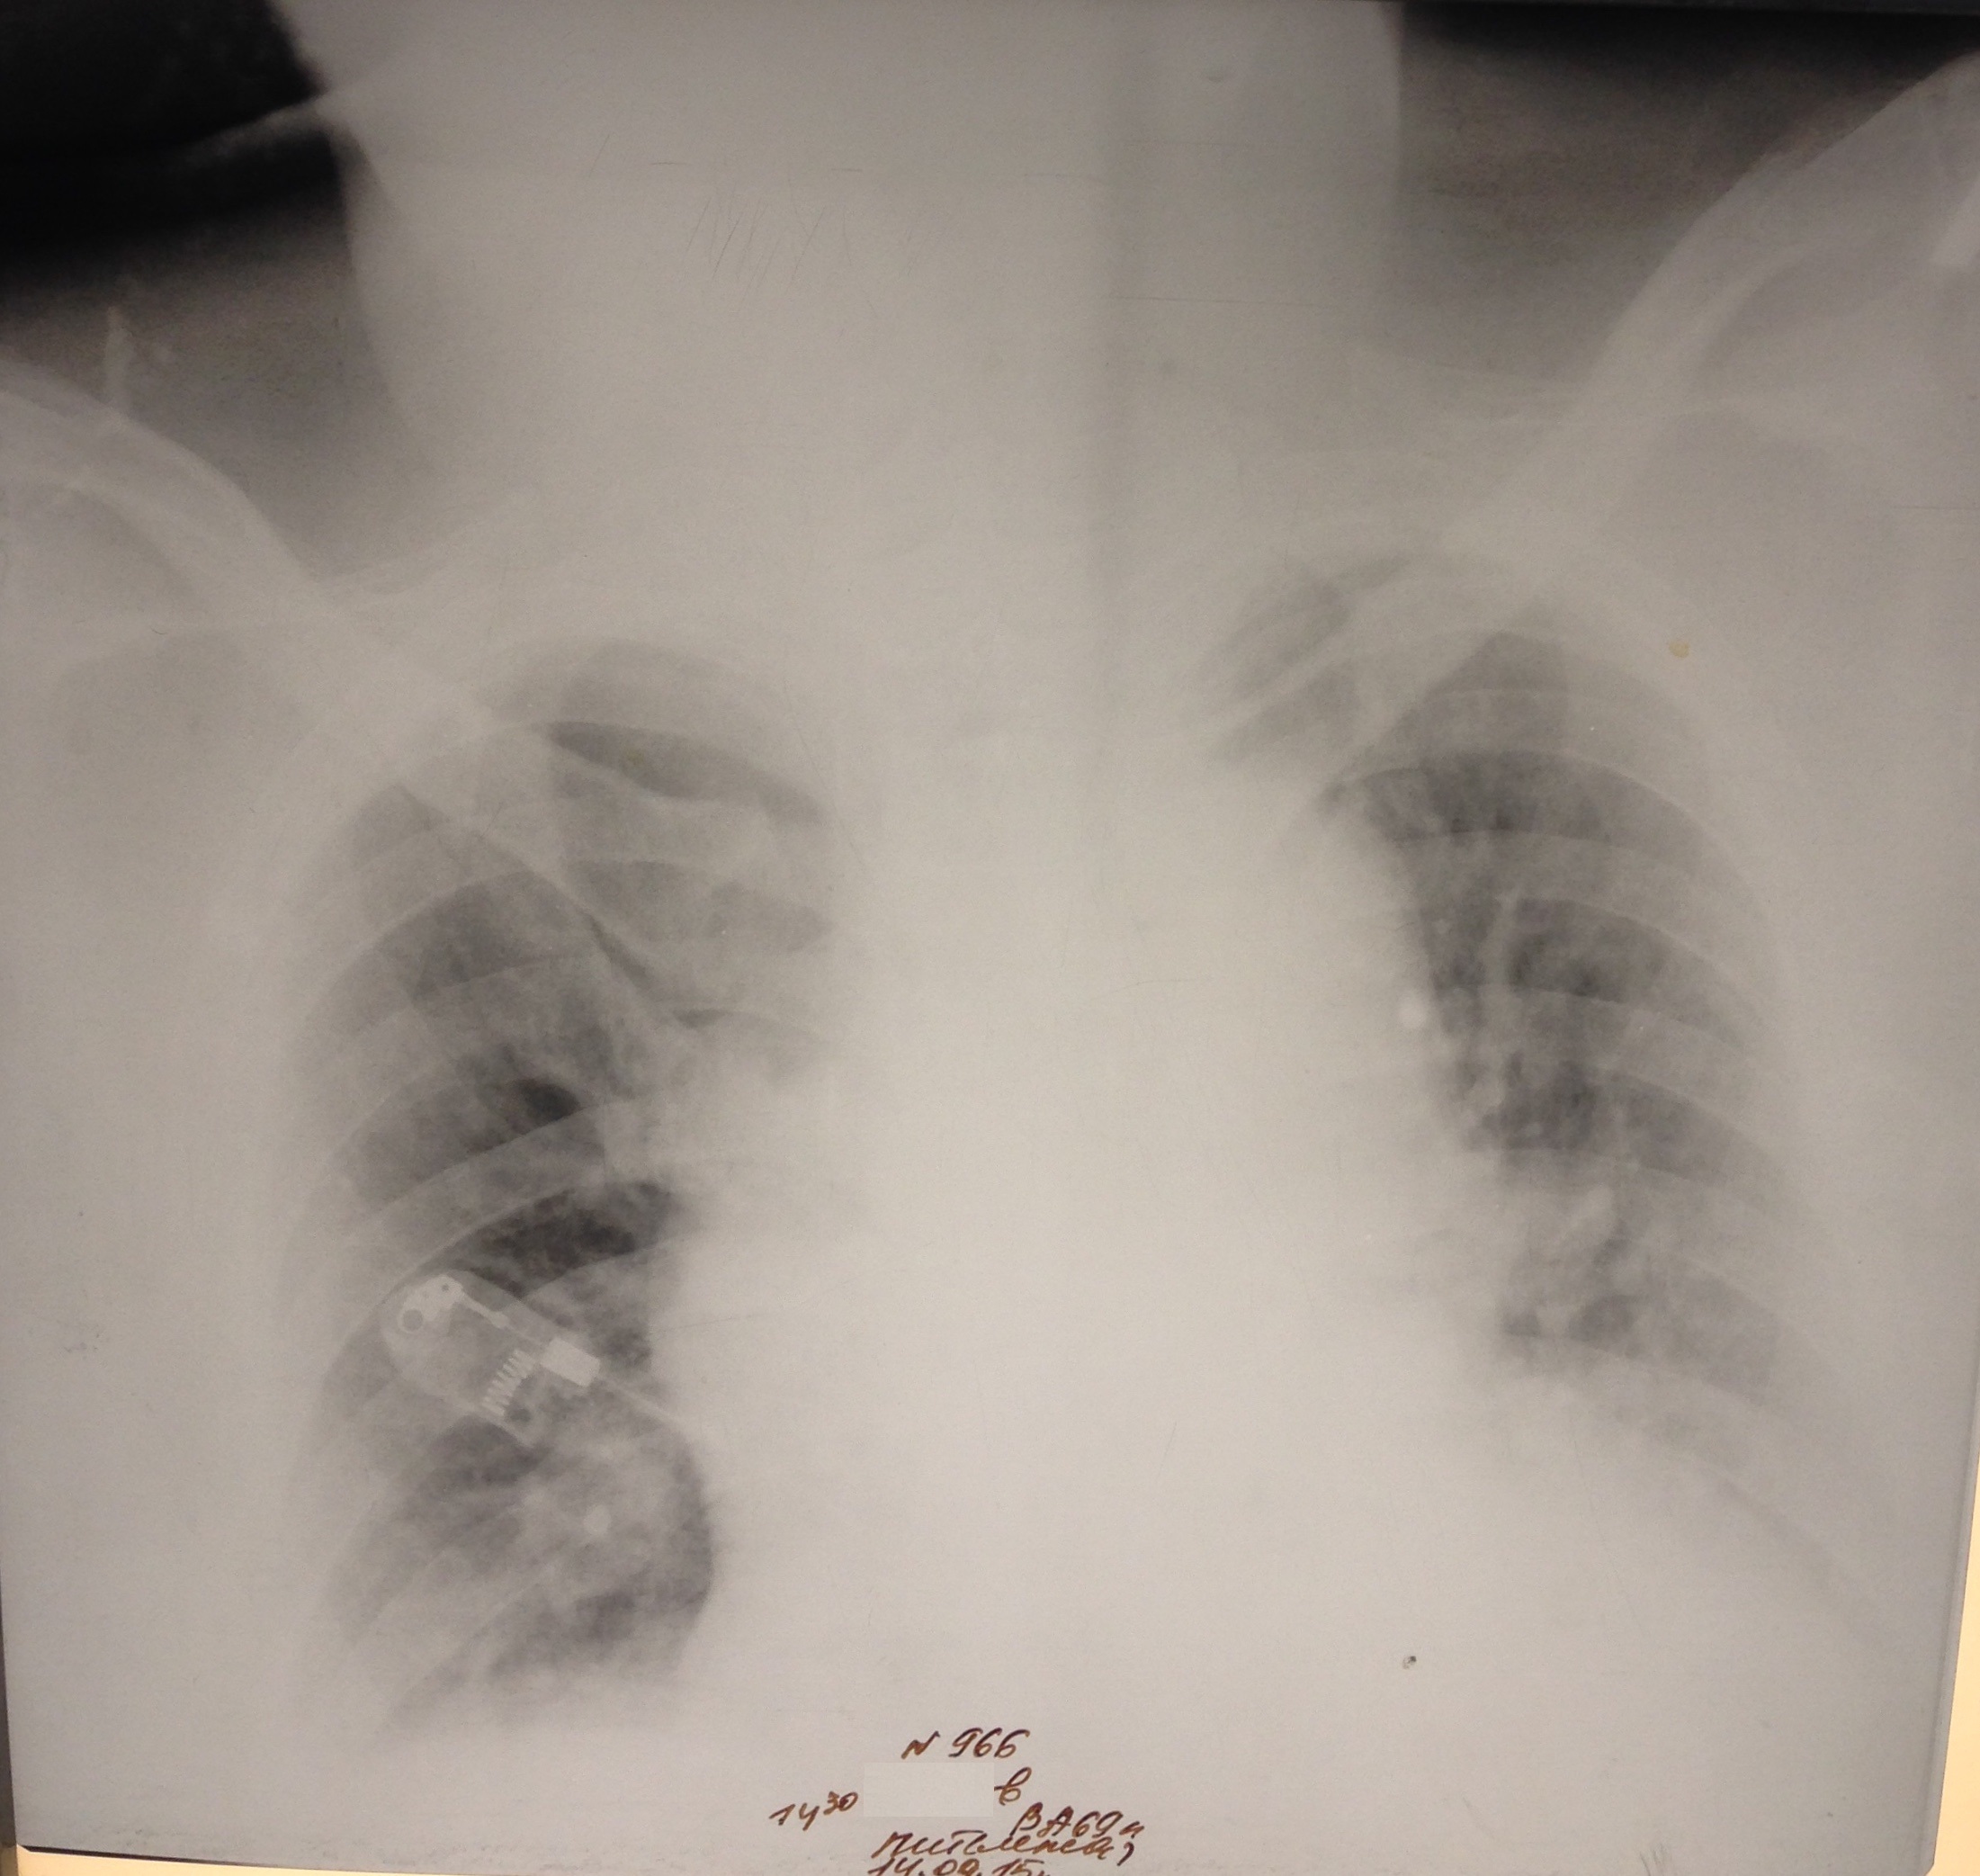

М, 69 лет. РАА. На первом снимке расширение срединной тени. На втором гемоторакс в результате прорыва крови из аорты в плевральную полость.

Ж 84 года. В маразме. РАА дуги и нисходящего отдела, доказана МСКТ. Поступила с болями в левом боку. На первом снимке левосторонний гемоторакс. На втором накопление жидкости до тотального уровня. На третьем после дренажа. Не оперирована. Выписана домой на 23 день госпитализации.